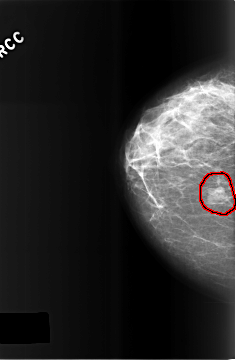

C_0510_1.RIGHT_CC

RIGHT_CC LINES 5760 PIXELS_PER_LINE 3776 BITS_PER_PIXEL 12 RESOLUTION 50 OVERLAY

FILE: C_0510_1.RIGHT_CC.OVERLAY

TOTAL_ABNORMALITIES 1

ABNORMALITY 1

LESION_TYPE MASS SHAPE OVAL MARGINS OBSCURED

ASSESSMENT 3

SUBTLETY 5

PATHOLOGY BENIGN

TOTAL_OUTLINES 1